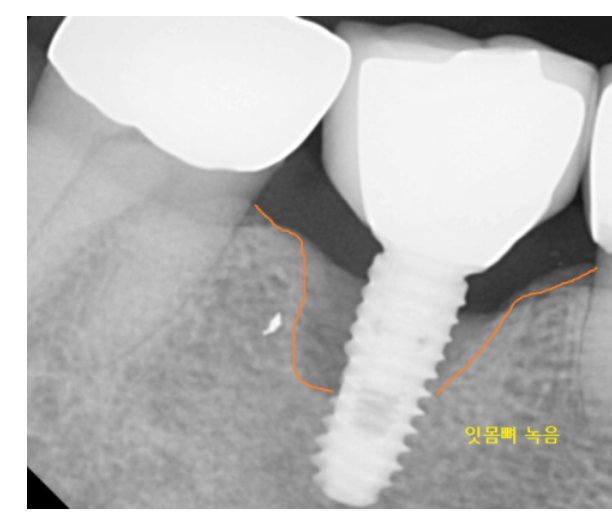

또한 임플란트 주변 골 소실에 심한 경우에도

수리하는 것이 의미가 없을 수 있습니다 .

이러한 경우엔 전체적인 진단 후

새로운 계획을 세우는 것이 필요합니다.